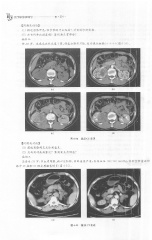

Page 240 - 医学影像诊断学